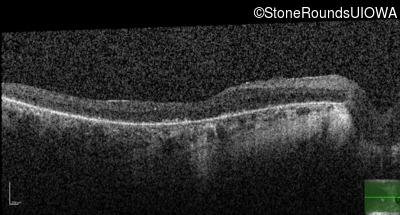

Optical Coherence Tomography - Left - 5/225

Exemplar / OCT Stack